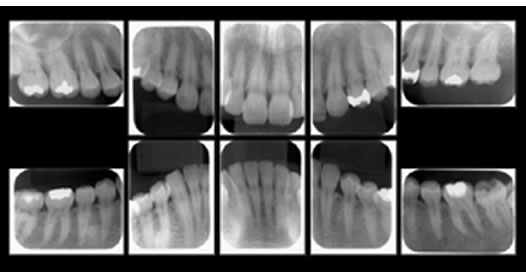

症例3

治療の特徴(患者I様)

初診 2015年5月1日 / 経過 2018年7月2日

| 治療期間 | 2年5カ月(2019年5月時点SPT中) |

|---|---|

| 費用 | 保険内治療 |

| 歯間外科処置 | 1ブロック約9,000円(3割負担) |

| 治療のデメリット | 外科処置を伴う・治療期間が長い(歯槽骨の安定を見る為) 歯周 外科処置後歯肉の位置が下がる為知覚過敏が起こりやすい |

X-Ray(レントゲン)写真

骨の状況、またむし歯の状態、咬み合わせによる歯牙への負担をチェックします。